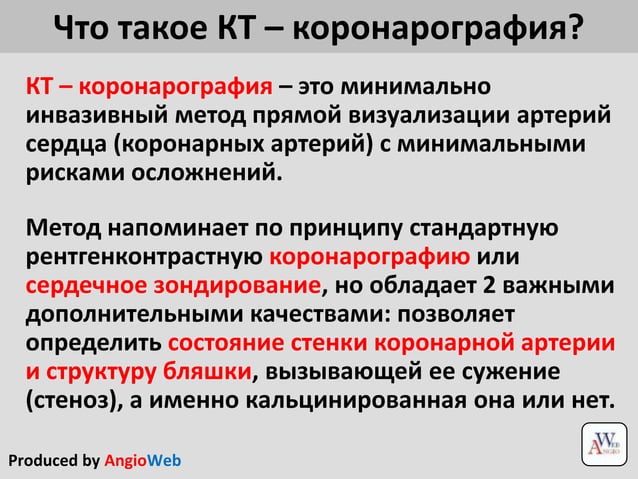

Что такое коронарография?

Коронарография — что это и зачем она нужна.